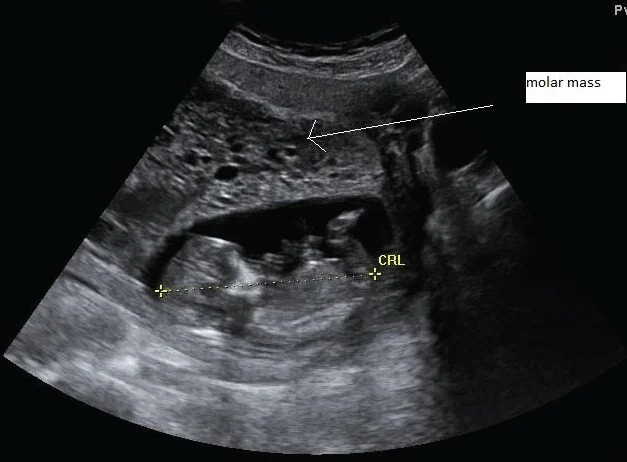

/attachments/image.webp)

Investigations

- US

-

Complete mole Hyperechoic multiple cysts filled the uterus (snowstorm appearance).

Partial mole Appear as missed miscarriage with cystic lesions in the placenta (sometimes), but definitive diagnosis when sending POC to chromosomal analysis.

/attachments/image-1.webp)

/attachments/Molar-Pregnancy-(GTD)-ps10-2.webp)

Choriocarcinoma

- Enlarged uterus.

- With highly vascular mass that invades the endometrium.

- And sometimes with areas of necrosis & cystic lesions.